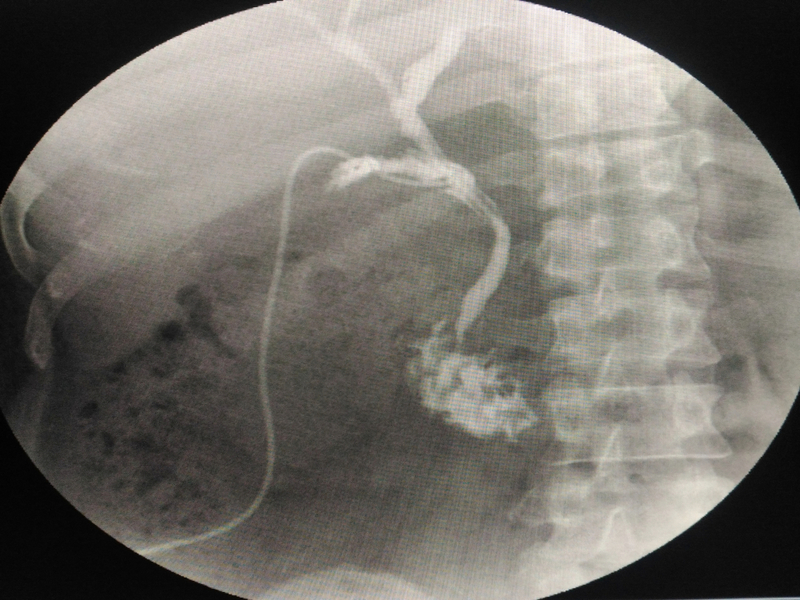

A resident of Padrauna in Uttar Pradesh's Kushinagar, looks normal at first glance but he is not. All the organs in his body are placed on the wrong side -- his heart is on the right side while his liver and gall bladder are on the left.

The matter came to light recently when the man complained of stomach ache and was taken to a doctor in Gorakhpur. The doctor was shocked to see the x-ray and ultrasound reports. Dr Shashikant Dixit, who is a bariatric laparoscopic surgeon, said, "We found stones in his gall bladder. But it is extremely difficult to take out the stones if the gall bladder is located on the left side. We had to take the help of three dimensional laparoscopic machines to perform the surgery."